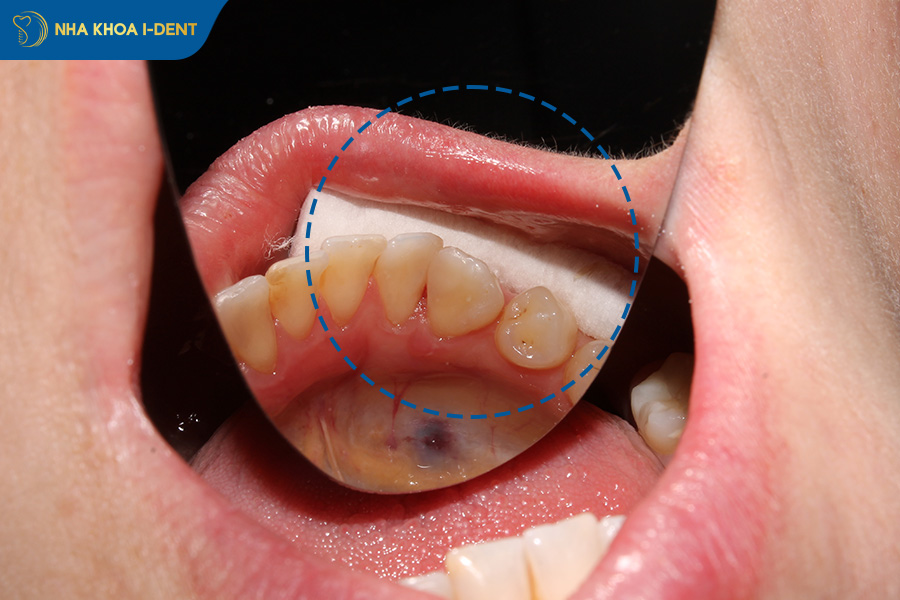

Vệ sinh răng miệng sau khi nhổ răng khôn là điều cần thiết để ngăn chặn vi khuẩn sinh sôi, bảo vệ cục máu đông và giúp vết thương mau lành. Cụ thể hơn, nếu bạn chủ quan trong việc chăm sóc, vi khuẩn từ thức ăn kẹt lại sẽ gây ra những vấn đề sau:

- Nhiễm trùng lan rộng: Vi khuẩn không được làm sạch sẽ lây sang các răng bên cạnh, gây viêm lợi hoặc thậm chí là nhiễm trùng máu rất nguy hiểm.